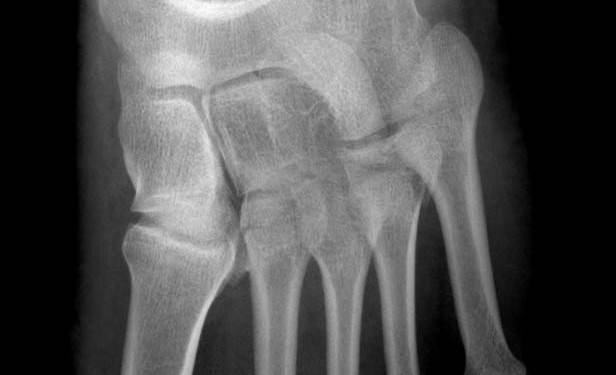

metatars fracture 2

2. metatars bazis kırığı